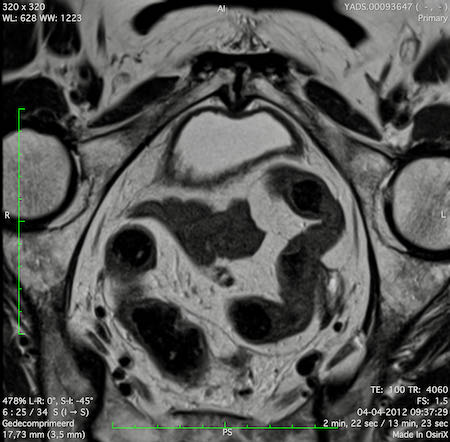

Hình ảnh

Các hình ảnh được cung cấp cho thấy ung thư biểu mô tế bào nhẫn với tình trạng dày lan tỏa thành trực tràng, hình ảnh bia bắn điển hình, và sự xâm lấn mỡ mạc treo trực tràng.